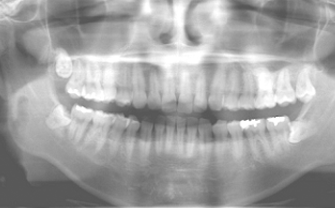

BioNaシミュレーション画像

BioNaシミュレーション画像 歯牙支持型フラップレス

歯牙支持型フラップレス